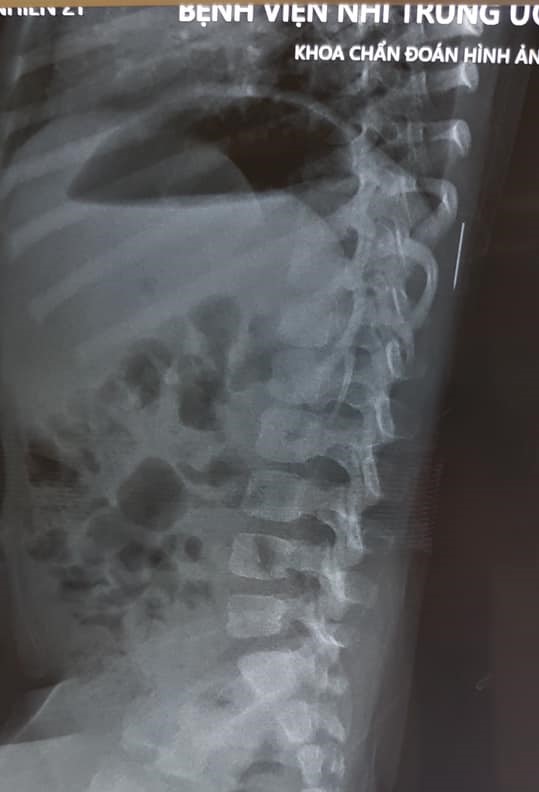

Tại Bệnh viện Nhi Trung ương, trong quá trình thăm khám, các bác sĩ đã tiến hành cho cháu chụp X-quang và phát hiện có dị vật trong phần mềm vùng cơ lưng trái, đốt sống 11.

Hình chụp X-quang